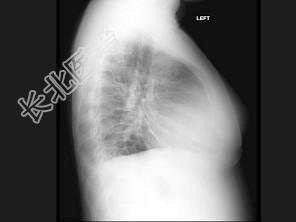

- 单项选择题女,17岁, 背部和正中胸部急性疼痛和带状疱疹感染,结合图像, 最可能的诊断是 ( )